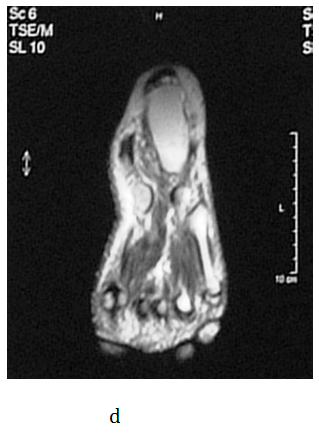

The operative and postoperative period passed without complications but she continued to have the same problems after the surgery. The patient received analgesic medications few months before she came to our Clinic. On her first visit at our outpatient clinic in July 2008, orthopedic shoes made on a plaster model of her feet with metatarsal pad were prescribed. On the control examination, the patient complained that the symptoms were worse and even disabling. An urgent MRI of the left foot was advised. The MRI showed a 2.5-centimeter in diameter, round, encapsulated mass that was differentially diagnosed as lipoma or neuroma (Figure 1a-1d). A surgical extirpation of the tumor was suggested. The operation was performed in September 2009 at the University Clinic for Orthopedic Surgery. At the level of the medial cuneiform bone of the foot, a round encapsulated mass, surrounding the medial communicant branch of medial plantar nerve was found (Figure 1e). Since the tumor could not be detached from the nerve, a neurectomy of the nerve proximal to the tumor was done. There were no complications in the operative and postoperative period. The excised tissue was sent for histological examination and the result confirmed it to be a Schwannoma (Figure 1f). After surgery, the patient was relieved of all symptoms. Follow-up visits were carried out at three, six and twelve months after the excision of the  Schwannoma. The patient had no pain and function of the left foot was normal at each consecutive control.

Figure 1 a, b) MRI cross section of the foot in T1 and T2 sequence (arrow shoving Schwannoma), c, d) MRI transverse section of the foot in T1 and T2 sequence e) macroscopic appearance of excised and cut in half Schwannoma f) Verocay body surrounded by Anthony B cells (HE, x100).